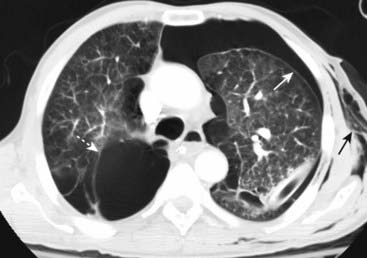

Figure 8-11 Bilateral pneumothoraces.

Conventional radiography is the initial modality used for detecting pneumothorax, but smaller pneumothoraces may be visible only on CT scans of the chest. This patient has bilateral pneumothoraces (solid white arrows). Air will rise to the highest point (the patient is supine in the CT scanner). Extensive subcutaneous emphysema also is present (solid black arrows); it developed because of an “air leak” from a chest tube that had been inserted earlier.